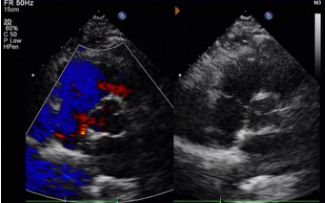

Gün 1 ila 9 ay:

Artık şant gözlenmedi.

Cihaz ekojenikliğinde kademeli azalma.